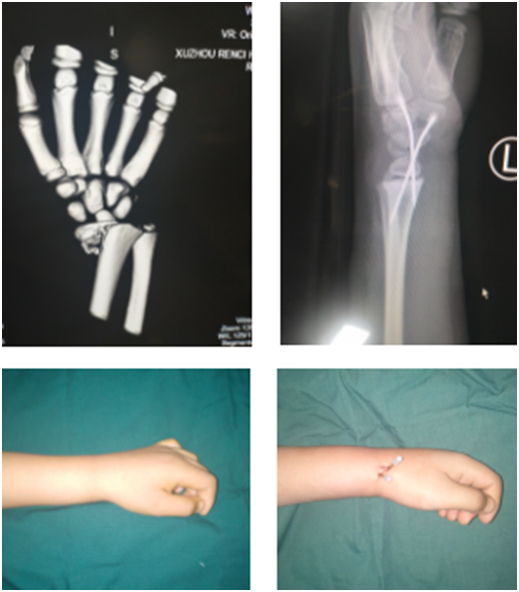

十歲的彥彥騎平衡車摔倒骨折

平衡車雖名為平衡車,但實際上考驗的是人的平衡能力。孩子的平衡能力差,自我保護意識也不強。一開始,彥彥慢慢地練習,后來隨著車技嫻熟加快了行駛速度,結(jié)果在一個急轉(zhuǎn)彎的時候,身體傾斜,一下子摔倒,彥彥只聽左手手腕處“咔嚓”一聲,感到一陣鉆心般的疼痛。

彥彥回到家跟媽媽講了自己騎平衡車摔倒的事情,說他的左手手腕不能動,媽媽趕緊帶他去醫(yī)院拍片,檢查發(fā)現(xiàn)左橈骨遠端骨折。當?shù)蒯t(yī)院沒辦法進行微創(chuàng)手術(shù),在醫(yī)生的建議下,他們到達仁慈。潘勇醫(yī)生手術(shù)團隊為彥彥進行手術(shù),術(shù)中切開1厘米縱形切口,閉合復(fù)位內(nèi)固定。這種微創(chuàng)手術(shù)切口小,恢復(fù)快,效果佳,還不用打石膏。術(shù)后三天,彥彥就出院了。